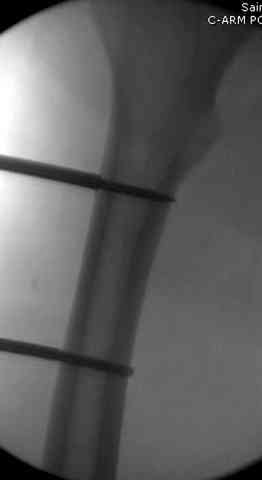

Я бы выполнил более стабильную фиксацию (а у меня есть подозрения в нестабильности отломков - компоновка минимальная, стержни проведены близко друг от друга, имеется выраженное воспаление тканей вокруг раны). Добавил бы стержни в данном аппарате или бы наложил спицестержневой аппарат.